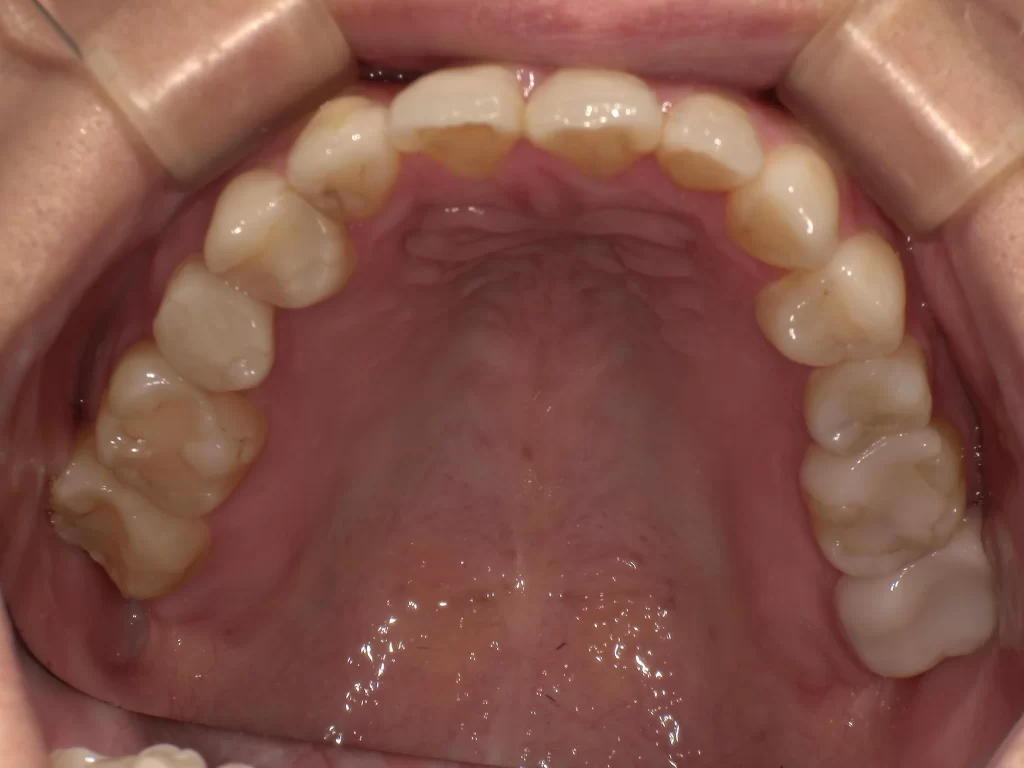

症例⑤:10歳・ガタガタ・出っ歯・深い噛み合わせ

【使用期間:3ヶ月】

歯が生えるスペースが足りずガタガタしており、噛み合わせも深い状態でした。

▼ 治療前(Before)

▼ 使用3ヶ月後(After)

- 年齢・症状: 10歳、叢生(ガタガタ)、過蓋咬合

- 治療法: プレオルソ

- 期間: 3ヶ月

- 結果: 装置を使うことで歯列の横幅が拡大し、ガタつきが自然に改善されました。深い噛み合わせも良くなっています。